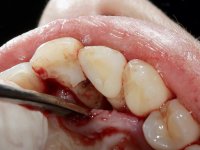

It was proposed to the patient to make a full-coated crown with a ceramic-coated Zr infrastructure that would aesthetically and functionally rehabilitate tooth 11. We decided not to redo the endodontic treatment given the absence of signs and symptoms for more than 20 years. The coronary structure would be previously reinforced with the placement of an intraradicular post and the making of a new restoration in composite resin. Periodontal pocket would be surgically addressed.

The treatment began with the placement of an intraradicular post and the creation of a new composite resin restoration. This procedure was performed with a surgical approach that allowed the remaining margins to be completely exposed, which were shown to be at a very infra-gingival level. Simultaneously, the periodontal pocket was curetted and root scaling and root planning of adjacent teeth were performed. Two months after this first intervention, the making of the crown began. A pre-print on silicone was performed to make a temporary crown with dual-cured composite resin. Gingival retraction was performed using the technique of kaolin paste compressed by the provisional crown. The impression was made using the double-mix technique with double viscosity with quick-setting silicone. In the laboratory, a crown with a ceramic-coated Zr infrastructure was made. The crown slightly overlapped tooth 12, allowing a dimensionally mimicry of the symmetrical tooth. Its fit was confirmed and approved by the patient; it was definitively cemented with resin-reinforced glass ionomer cement.